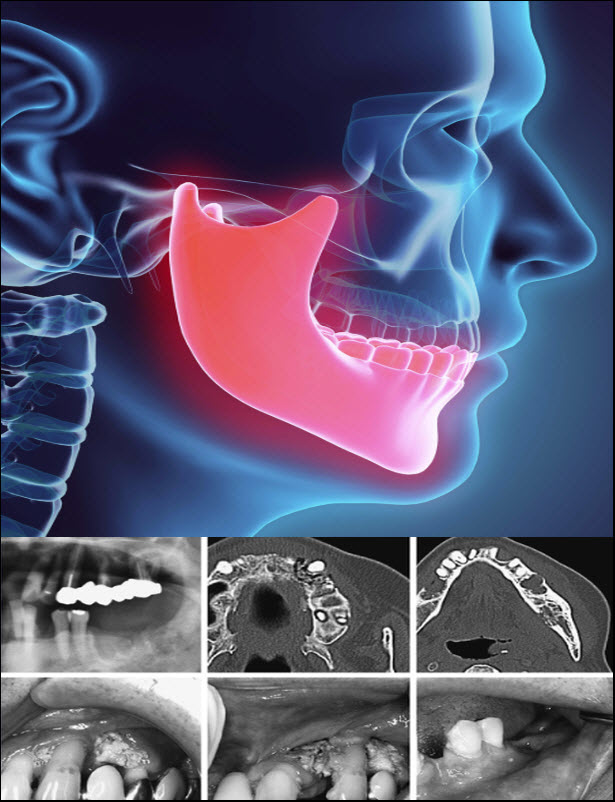

Bazal hücreli karsinom nasıl teşhis edilir?

Cilt lezyonunun görünümüne bağlı olarak, sağlık uzmanınız bazal hücreli karsinom teşhisinden hemen şüphelenebilir. Teşhisi doğrulamak için sağlayıcınız fiziksel bir muayene yapacak ve size belirtileriniz hakkında aşağıdakiler dahil sorular soracaktır:..)Kaynak © 2023 Cleveland Klinik.

Hangi testler bazal hücreli karsinomu teşhis eder?

Fiziksel bir muayeneden sonra, sağlayıcınız bir teşhisi doğrulamak için aşağıdakileri içerebilecek testler sunabilir:..)Kaynak © 2023 Cleveland Klinik.

Cilt biyopsisi : Sağlayıcınız, mikroskop altında incelemek için etkilenen cilt bölgesinden (lezyon) bir parça alacaktır.

Görüntüleme testleri: Bazal hücreli karsinomun vücudunuza yayılması son derece nadirdir. Sağlık uzmanınız, kanserinizin vücudunuzun herhangi bir yerine yayıldığından şüphelenirse, lenf düğümlerinde veya iç organlarda kanseri saptamak için bir MRI veya CT taraması yapabilir.

Sağlayıcınız, fizik muayene yaptıktan ve testlerinizin sonuçlarını inceledikten sonra teşhisinizin aşamasını belirleyecektir. Aşamayı belirlemek için elemeler şunları içerir:

Lezyonun (tümör) büyüklüğünü belirleme ve dokularınıza daha derine inip büyümediğini belirleme.

Lenf düğümlerinde kanser belirtileri aramak.

Kanserin yayılıp yayılmadığını (metastaz yapmış) görmek için vücudunuzun diğer bölgelerini kontrol etmek.

Lezyonun boyutunu, şeklini ve yerini ölçmek ve büyüme hızını kaydetmek…)Kaynak © 2023 Cleveland Klinik.

Bazal hücreli karsinom nasıl tedavi edilir?

Sağlayıcınız, kanseri vücudunuzdan çıkararak bazal hücreli karsinomu tedavi edecektir. Kanseri ortadan kaldırmak için tedavi seçenekleriniz şunları içerebilir: